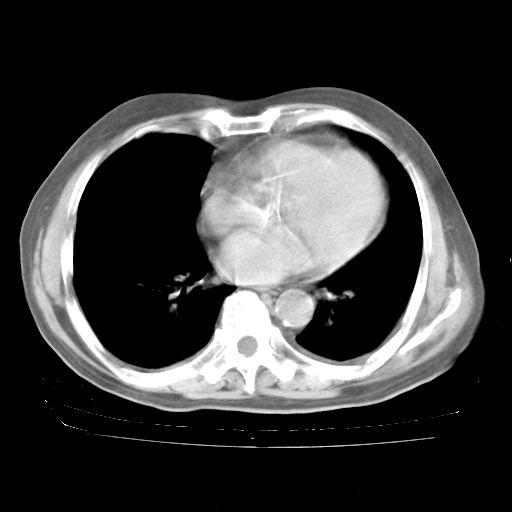

4月28日肺部CT——再次出现类似去年5月9日——透光度降低,“间质性”改变。